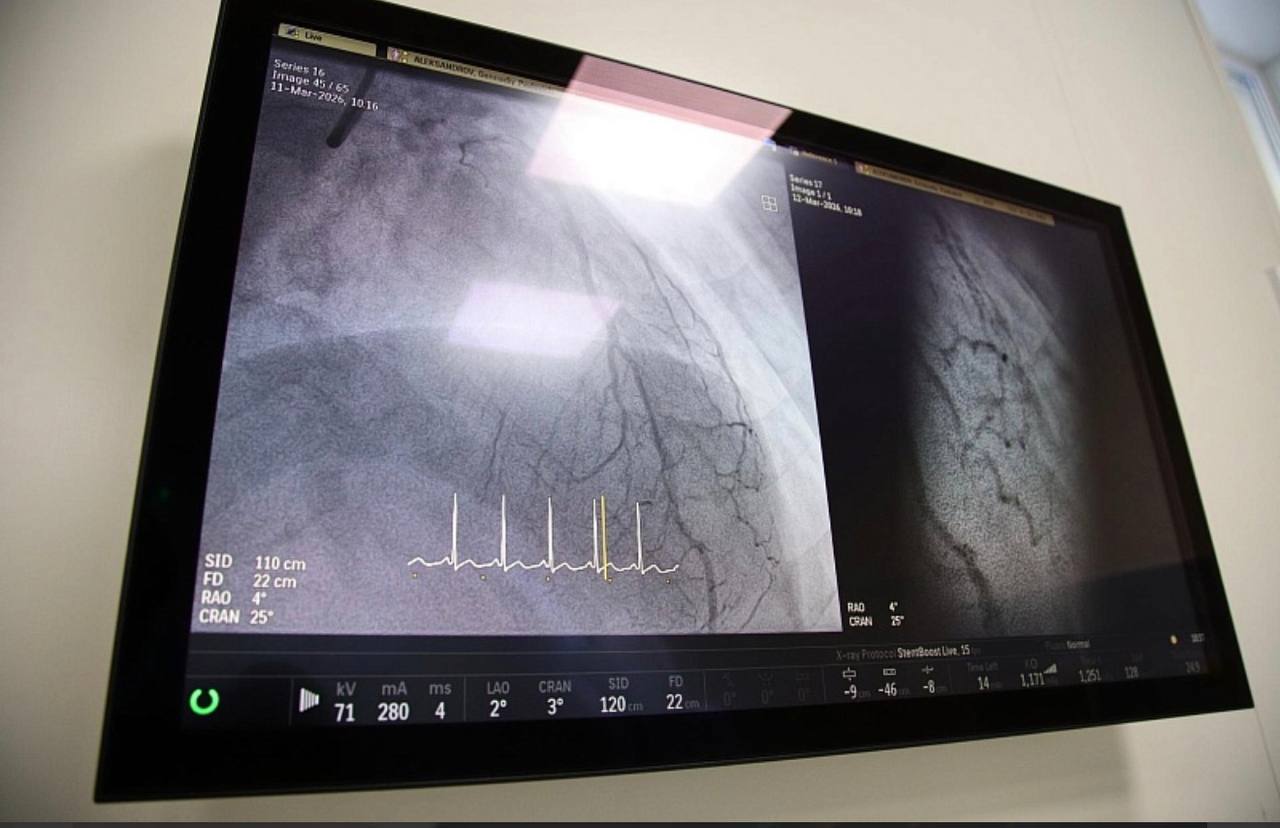

«Операция включала в себя стентирование коронарных артерий, а именно сосудов сердца, от которых у него случился инфаркт миокарда. Пациенту уже выполняли такую операцию 11 лет назад в другом городе, после этого к врачам он не обращался, таблетки принимал нерегулярно. К нам поступил в критическом состоянии. Из-за высокой степени тяжести патологии пациент был экстренно направлен из приемного покоя сразу в операционную», – рассказал заведующий центром Гурген Айвазян.

Сложность вмешательства заключалась в том, что операция, продлившаяся около часа, проводилась параллельно с сердечно-легочной реанимацией. Несмотря на критическую ситуацию, врачам удалось выполнить имплантацию двух новых стентов.

Качественное проведение операции стало возможным благодаря использованию новейшего ангиографического комплекса и метода оптической когерентной томографии (ОКТ). Новая операционная, высокоточное оборудование, позволяющее проводить вмешательства с максимальной эффективностью, поступило в Воскресенскую больницу по поручению губернатора Московской области Андрея Воробьева в рамках реализации нацпроекта «Продолжительная и активная жизнь» при поддержке министерства здравоохранения Московской области.